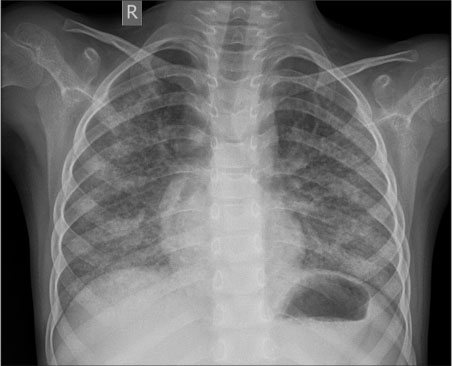

A 4-year-old boy with B-acute lymphoblastic leukemia on maintenance chemotherapy presented with acute-onset respiratory distress along with a fever of 2 days duration. At the time of admission, he was tachypneic with a respiratory rate of 56/min and hypoxic with a room air saturation of 77%. His chest X-ray was suggestive of bilateral pneumonitis [Figure 1] and his blood investigations revealed a total white blood cell (WBC) count of 0.9 × 109 cells/L with an absolute neutrophil count (ANC) of 0.2 × 109 cells/L. He was diagnosed as having febrile neutropenia with pneumonia and started on piperacillin-tazobactam, azithromycin, cotrimoxazole, and vancomycin, to provide coverage for the Gram-negative, Gram-positive, and atypical microorganisms including Pneumocystis jirovecii. Oseltamivir was also added considering the epidemic of H1N1 Infuenza virus in the community. The chemotherapy medications (6 mercaptopurine and methotrexate) were withheld. With oxygen supplementation at 2 L/min, he maintained a SpO2 of 98%. Considering the hypoxia, methylprednisolone was also started. As the fever persisted even after 96 h of admission, conventional amphotericin B was also added. On the 4th day of admission, his WBC count increased to 2.4 × 109 cells/L (ANC 1.5 × 109 cells/L), without the use of granulocyte colony-stimulating factors. His blood cultures never grew any organisms. His symptoms progressed in the form of worsening tachypnea and hypoxia requiring oxygen flow at 4 L/min. His repeat chest X-ray showed a diffuse infiltrative pattern with ground glassing. At this point, CMV quantitative real-time PCR was sent, and antibiotics were upgraded to meropenem. However, it was decided to withhold adding intravenous (IV) ganciclovir until disease confirmation or further deterioration. In the next 2 days, the child became afebrile and his general condition improved, except for minimal tachypnea and persistent hypoxia. We were unable to withdraw his oxygen support, even though he maintained a saturation of 98% with 1 L/min oxygen support. By the 14th day of admission, his CMV quantitative real-time PCR was reported as high positive (9.2 × 105 IU/ml, normal value <363 xss=removed>th day of admission after restarting his maintenance chemotherapy. Awaiting the repeat CMV DNA PCR report and fearing for worsening of pneumonia, he was discharged on oral valganciclovir. At follow up after two weeks, valganciclovir was stopped as his CMV DNA PCR was reported to be normal (< 363>

| Figure 1 Pneumonitis noted with involvement of both lungs in the form of diffuse reticular shadowing and patchy infiltrates|